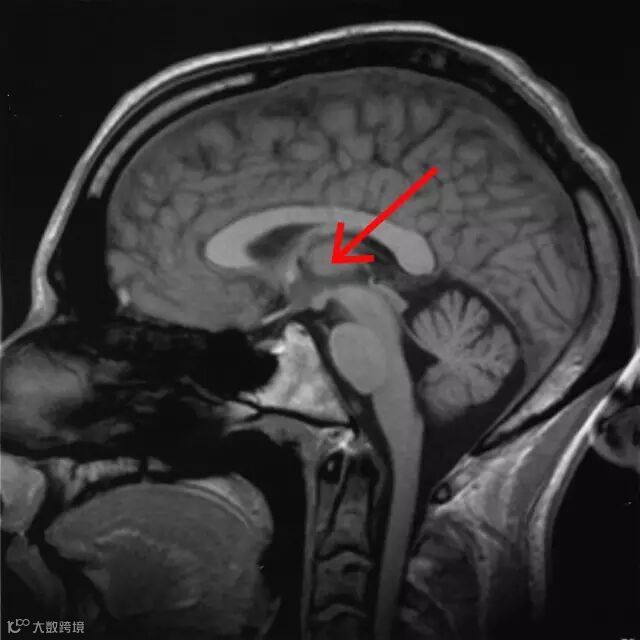

核磁共振成像人脑的矢状切面,红色箭头处为丘脑 来源:维基百科